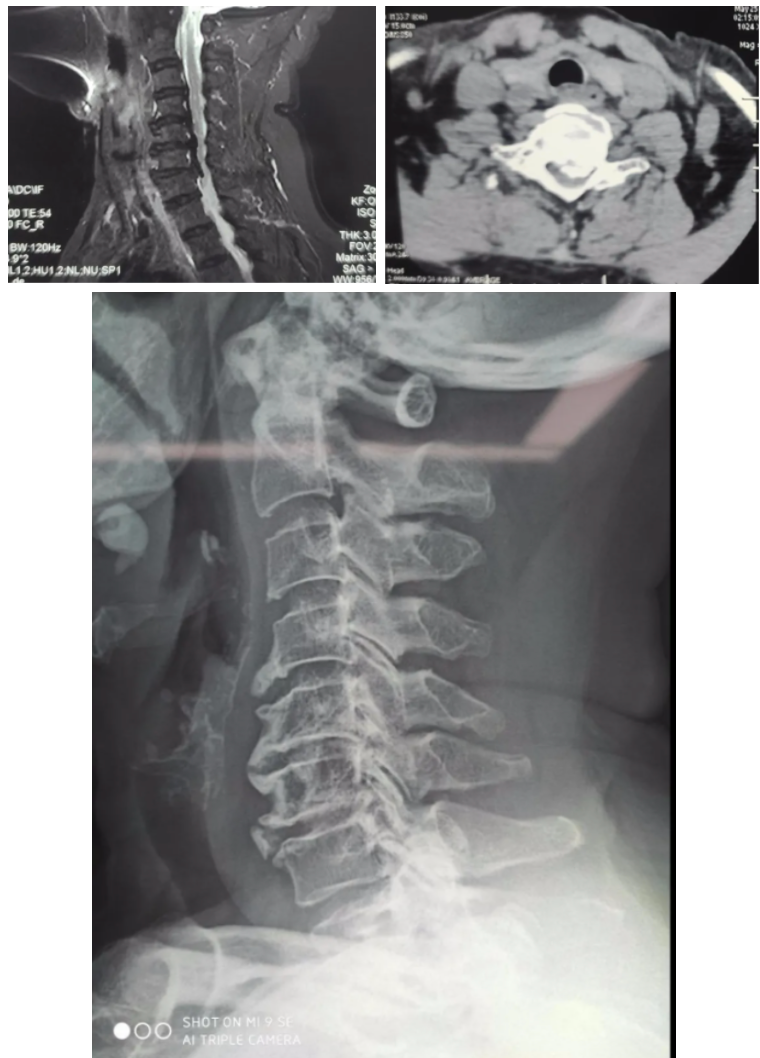

¿ËÈÕ£¬£¬£¬£¬£¬Õ㽹㻪ҽԺ¼¹Öù¿ÆÔÚÌìçá?¹Ç¿ÆÊÖÊõ»úеÈ˵ĸ¨ÖúÏÂÍê³ÉÁËһ̨¼¹ËèÐ;±×µ²¡¾±×µºó·׵¹¸ùÂݶ¤ÄÚÀο¿+¼õѹÈÚºÏÊÖÊõ¡£¡£¡£¡£¡£¡£¡£ÒÔÍù¾±×µºó·ÄÚÀο¿ÊÖÊõÄѶȴóΣº¦¸ß£¬£¬£¬£¬£¬ÏÖ½ñÔÚÌìçá?¹Ç¿ÆÊÖÊõ»úеÈ˵Ä×ÊÖúÏ£¬£¬£¬£¬£¬½µµÍÁ˾±×µºó·ÄÚÀο¿µÈÊÖÊõµÄÊÖÒÕÃż÷£¬£¬£¬£¬£¬Îª¿í´ó»¼Õß´øÀ´¸£Òô¡£¡£¡£¡£¡£¡£¡£

ÀîÔº³¤ÏÈÈÝ£¬£¬£¬£¬£¬¼¹ËèÐ;±×µ²¡ÊÇÓɶàÖÖÒòËØµ¼Ö¾±×µ×µ¹ÜÏÁÕեȡ¼¹Ë裬£¬£¬£¬£¬»¼Õß»á׿¹ËèÊÜѹ¼°±äÐÔµÄˮƽ¼ÓÖØ£¬£¬£¬£¬£¬Öð½¥·ºÆðË«ÏÂÖ«²ÈÃÞ¸ÐÂéľ·¦Á¦Ë«ÊÖÂéľ·¦Á¦£¬£¬£¬£¬£¬ºóÆÚÉõÖÁ¿É·ºÆð½ØÌ±¾Þϸ±ãʧ½ûµÈÇéÐΡ£¡£¡£¡£¡£¡£¡£·¶°¢ÆÅ¼´ÊÇÓÉ×µ¼äÅ̺óÔµ´ó×Ú¹ÇÖÊÔöÉúեȡ¼¹ËèÒýÆðµÄ£¬£¬£¬£¬£¬¹ØÓÚÕâÖÖ¹ÇÖÊÔöÉúÑÏÖØµÄ²¡ÈË£¬£¬£¬£¬£¬¾±×µÇ°Â·ÊÖÊõÎÞ·¨Íê³É¼õѹ£¬£¬£¬£¬£¬Ö»ÄÜÐо±×µºó·ÈںϼõѹÄÚÀο¿ÊÖÊõ¡£¡£¡£¡£¡£¡£¡£

¾±×µºó·ÊÖÊõÖ®ÒÔÊǽÏǰ·ÊÖÊõΣº¦¸üºÆ½Ù¶È½Ï¸ß£¬£¬£¬£¬£¬³ýÁËÌåÏÖÔÚ¼õѹʱÈÝÒ×ËðÉËÉñ¾Ö®Í⣬£¬£¬£¬£¬ÉÐÓÐÒ»¸öÖ÷ÒªµÄµã¼´ÊǾ±×µµÄ×µ¹¸ù½Ïϸ£¬£¬£¬£¬£¬Âݶ¤Ö²Èëʱ¹ØÓÚÖö¤µãºÍÖö¤½Ç¶ÈµÄÒªÇ󼫸ߣ¬£¬£¬£¬£¬ÉÔÓÐʧÉ÷¾Í»á·ºÆðÎó²î£¬£¬£¬£¬£¬ËðÉËÉñ¾¼°Ñª¹Ü£¬£¬£¬£¬£¬ÉõÖÁÓÚΣ¼°ÉúÃü£¬£¬£¬£¬£¬¶øÕâÖÖΣº¦ÔÚÓÐÁËÌìçá?¹Ç¿ÆÊÖÊõ»úеÈ˸¨Öúºó£¬£¬£¬£¬£¬½èÖúÌìçá?¹Ç¿ÆÊÖÊõ»úеÈ˾«×¼µÄ¶¨Î»¼°Ö¸µ¼£¬£¬£¬£¬£¬ÕâÖÖΣº¦¿É´ó´ó½µµÍ¡£¡£¡£¡£¡£¡£¡£